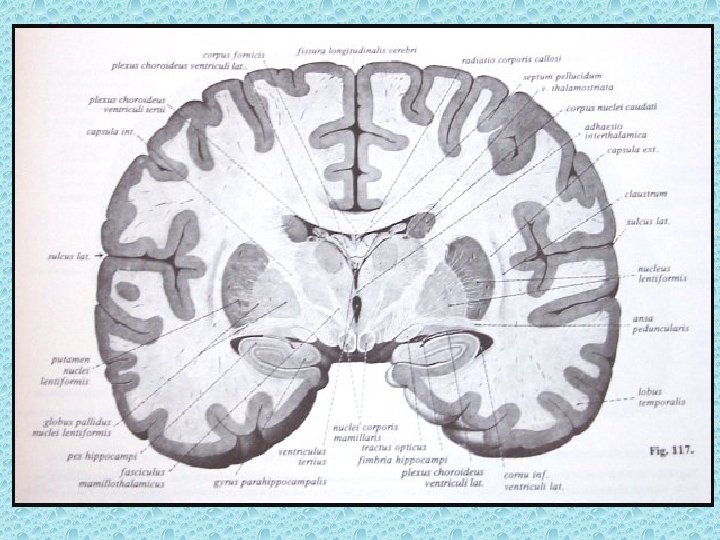

SEREBRAL PARANKİMDE BULUNAN YAPILAR • • Beyaz ve gri cevher Girus ve sulkuslar Lentiform nükleus: Putamen ve globus pallidus İnternal ve eksternal kapsül Talamus Kaudat nükleus ve korpus kallozum Ventriküller Koroid pleksus

VENTRİKÜLLER • Lateral ventriküller: frontal, oksipital ve temporal hornlar, korpus ve atrium • Foramen monro • 3. Ventrikül • Akuaduktus silvii • 4. Ventrikül • Foramen Lucka (çift) ve magendi (tek)